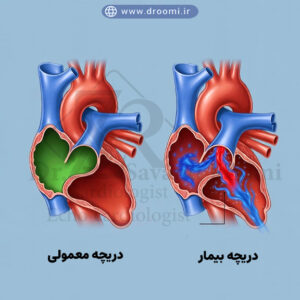

تصویر آموزشی که تفاوت دریچه سالم و دریچه دارای نارسایی را با جریان خون رنگی نشان میدهد.

بیماریهای دریچه قلب به گروهی از اختلالات اشاره دارد که عملکرد دریچههای قلب را مختل میکنند و میتوانند منجر به مشکلات جدی مانند نارسایی قلبی شوند. این بیماریها ممکن است مادرزادی باشند یا در اثر عفونتها، بیماریهای روماتیسمی، یا حتی افزایش سن ایجاد شوند. علائم رایج شامل خستگی، تنگی نفس، تورم پاها و ضربان قلب نامنظم است که اگر نادیده گرفته شوند، میتوانند عواقب جبرانناپذیری به همراه داشته باشند. در این میان، نارسایی دریچه قلب یکی از شایعترین مشکلات است که در آن دریچهها به درستی بسته نمیشوند و خون به عقب بازمیگردد، پدیدهای که به عنوان رگورژیتاسیون شناخته میشود.

بیماریهای دریچه قلب از جمله اختلالات رایج قلبی-عروقی هستند که میتوانند کیفیت زندگی افراد را به طور قابل توجهی تحت تأثیر قرار دهند. این بیماریها عمدتاً به دو دسته اصلی تقسیم میشوند: نارسایی دریچه قلب (رگورژیتاسیون، که در آن دریچه به درستی بسته نمیشود و خون به عقب بازمیگردد) و تنگی دریچه (استنوز، که دریچه تنگ شده و جریان خون را محدود میکند). تشخیص زودهنگام این مشکلات با استفاده از اکوکاردیوگرافی داپلر دریچه قلب و تصاویر اکو داپلر رنگی دریچههای قلب امکانپذیر است و در مراکز پیشرفته مانند کلینیک دکتر سوندرومی در شیراز، با دقت بالا انجام میشود. در ادامه به بررسی انواع شایع این بیماریها میپردازیم.

رگورژیتاسیون (نارسایی) دریچه آئورت و میترال از شایعترین انواع نارسایی دریچهای هستند. در نارسایی دریچه میترال، خون از بطن چپ به دهلیز چپ بازمیگردد که میتواند ناشی از آسیب لتها، عفونت یا بیماریهای زمینهای باشد. این مشکل اغلب با اکو رنگی نارسایی دریچه میترال به وضوح قابل مشاهده است، جایی که جریان خون بازگشتی به صورت جت رنگی ظاهر میشود.